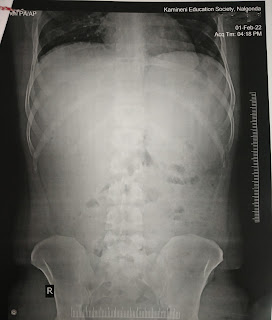

Abdomen PA/AP